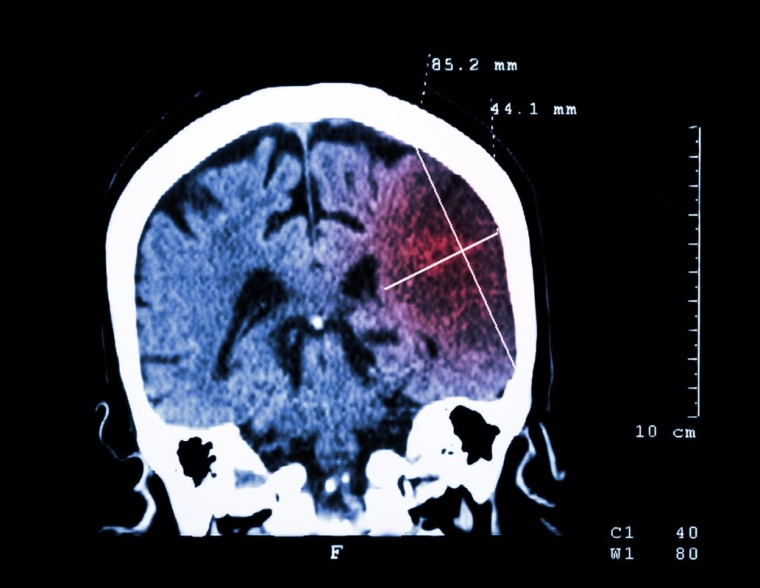

Das Problem: Für die Entscheidung zur Thrombektomie braucht es zunächst eine genaue Bildgebung des Gehirns per Computertomographie (CT). Damit lässt sich ein Gefäßverschluss bestimmen und eine Hirnblutung ausschließen, die etwa 20 Prozent aller Schlaganfälle verursacht. Üblicherweise wird der Patient nach der CT-Untersuchung in eine Angiographieanlage gebracht, wo Neuroradiologen in einem zweiten Schritt das verstopfte Gefäß öffnen. Moderne Angiographieanlagen versprechen hier Zeitgewinn: Sie ermöglichen auch die CT-Diagnostik vor Ort – eine separate CT-Untersuchung mit Transport und Umlagern entfällt also.